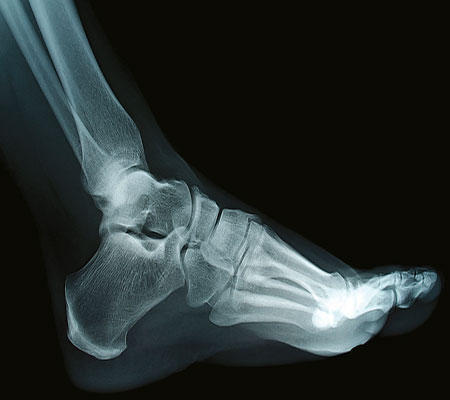

كما يشير اسمه، يكون مطبب الأرجل متخصصاً بالأقدام. يعالج مشاكل الأظفار والبشرة، فضلاً عن جميع الإصابات المرتبطة ببنية القدم وطريقة المشي. لا داعي للحصول على وصفة طبية من أجل زيارة هذا الاختصاصي.

تشمل المعاينة فحصاً شاملاً للقدم ووضعيتها ثم اقتراح علاجات للتخلص من الجلد الميت وقص الأظفار. لا تتعلق معالجة الأقدام بالجانب الجمالي الذي تتولاه اختصاصية التجميل. يعالج مطبب الأرجل فرط التقرن مثل الجلد الميت أو مسامير القدم التي تظهر في مناطق الضغط والاحتكاك في القدم وقد تسبب الألم أو حتى تلتهب إذا لم تتم معالجتها بالشكل المناسب. يتولى مطبب الأرجل أيضاً معالجة الثآليل والفطار والأظفار الغارزة في الجلد أو مشاكل التعرق.

يمكن أن يصنّع مطبب الأرجل معدات من السيليكون للحد من تطور إبهام القدم الأروح. ولمعالجة أي خلل في بنية القدم أو في طريقة المشي، قد يصنّع نعلاً للأحذية بناءً على وصفة طبية من اختصاصي أمراض الروماتيزم. تسمح هذه التصاميم بتخفيف أوجاع العضلات أو الأربطة أو المفاصل التي يمكن أن تؤثر سلباً على المشي.